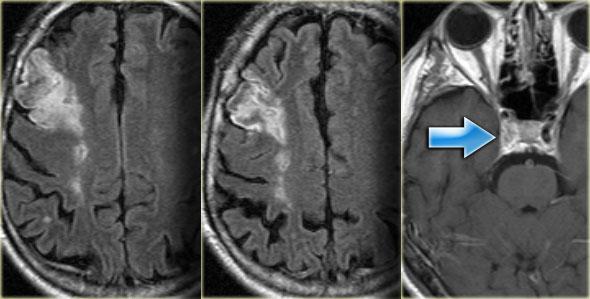

Bên trái là hình ảnh CT của nhồi máu PICA bên trái.

Lưu ý sự lan rộng về phía sau.

Nhồi máu là hậu quả của một trường hợp bóc tách động mạch (mũi tên xanh lam).

Bên trái là hình ảnh MRI của nhồi máu PICA bên trái.

Trong các trường hợp nhồi máu một bên, luôn có sự phân định rõ ràng tại đường giữa do các nhánh nhung mao trên không vượt qua đường giữa mà đi theo hướng dọc (sagittal).

Sự phân định rõ ràng này có thể không biểu hiện cho đến giai đoạn muộn của nhồi máu.

Trong giai đoạn sớm, phù nề có thể vượt qua đường giữa và gây khó khăn cho chẩn đoán.